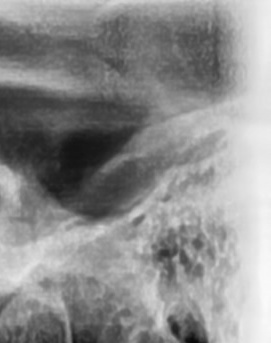

어금니 뒤 잇몸 부음의 문제는 사랑니가 원인이 되는 경우도 많은데 사랑니는 특히 현대인들의 경우 제대로 나오지 못하고 매복되는 경우가 많으며 완전히 나오지 않은 사랑니는 잇몸 속에서 자라면서 주변 잇몸을 자극할 수 있고, 일부만 노출되면 음식물이 끼면서 염증이 생기기도 하며 특히 어금니 뒤쪽 잇몸이 붓고 지속적으로 불편함을 느낀다면 사랑니로 인한 염증을 의심해 볼 수 있어요. 사랑니로 인한 문제의 경우 단순한 소염제나 구강 세정제로 해결되지 않고, 사랑니를 발치해야 잇몸 염증이 해결되는 경우가 많이 있어요

결론적으로는 통증이 심하거나 염증이 오래 지속되는 경우에는 치과를 방문해서 정확한 진단을 받는 것이 중요한데 단순한 잇몸 염증이라면 치석 제거와 항생제 치료로 호전될 수 있지만, 치주염이 진행된 경우라면 보다 적극적인 치료가 필요할 수 있어요. 만약 사랑니로 인해 잇몸이 자꾸 붓는다면 사랑니 발치를 고려해야 하겠고 사랑니가 완전히 매복되어 있다면 수술적인 방법으로 제거해야 할 수도 있어요. 특히 반복적으로 붓는다면 사랑니 검사를 받아보거나, 치과에서 정밀 검진을 통해 치주 상태를 확인하는 것이 필요하다는 점에서 어금니 근처의 잇몸이 반복적으로 불편하다면 꼭 치과를 찾아보시길 바라고 있어요